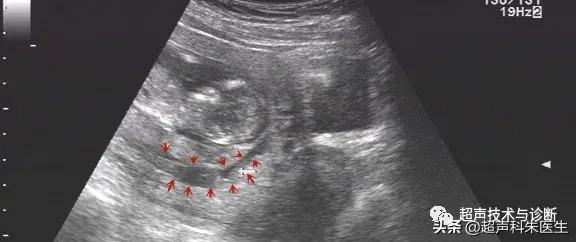

出现绒毛膜下血肿的孕妇,仅有20%会出现阴道不规则流血或下腹部疼痛的症状,而其余大多数绒毛膜下血肿是在超声检查中发现的,其超声表现为:子宫壁和胎膜(或孕囊)之间的无回声区,多位于胎盘下缘至宫颈内口间,以弧形或新月形多见,若血肿较多或血肿形成时间较长时,内可见点、絮状弱回声及条带状强回声,彩色多普勒超声检查:血肿内无血流信号。

根据绒毛膜下血肿的大小和范围,可对其进行定量分型:①小型血肿:妊娠囊周围绒毛膜下血肿的长度小于妊娠囊周长的20%;②中型血肿:妊娠囊周围绒毛膜下血肿的长度为妊娠囊周长的20~50%;③大型血肿:妊娠囊周围绒毛膜下血肿的长度大于妊娠囊周长的50%,或血肿的容积(长x宽x高÷2)>30ml。

接下来我们来看看具体病例: